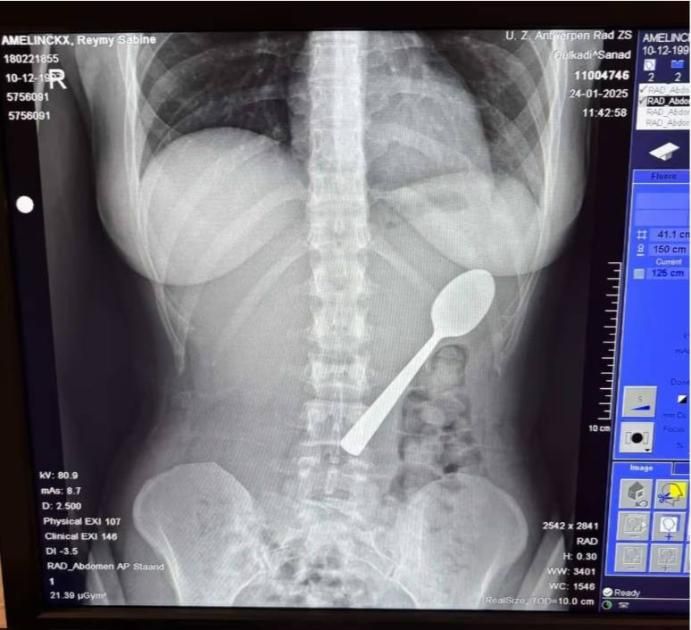

خضعت البلجيكية ريمي أميلينكس، 28 عاماً، لعملية صغيرة لإخراج ملعقة طولها 17 سنتيمتراً ابتلعتها عن طريق الخطأ، بعد أن قفز كلبها عليها بشكل مفاجئ أثناء تناولها الزبادي.

وأضافت: «كنت مندهشة للغاية، وقبل أن أدرك الأمر كانت الملعقة عالقة في حلقي، وحاولت إزالة الملعقة بيدي لكنني لم أستطع، ولم أشعر إلا وبها تنزلق إلى معدتي».

وبعد يومين، أزيلت الملعقة تحت التخدير الموضعي، ورغم أن العملية تسببت في نزيف بسيط لكنها شعرت براحة كبيرة بعد إخراجها، ولم تعانِ أي مضاعفات دائمة، وعادت إلى حياتها الطبيعية بعد ساعات قليلة، واكتسبت لقب الفتاة ذات الملعقة بين زملائها في العمل.